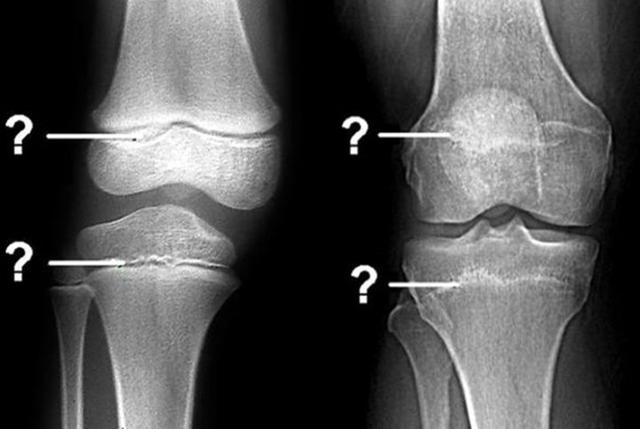

骨骺线闭合是孩子“身高”封锁的信号 , 要想蹿出高个子 , 家长要有数在一些家长看来 , 判断孩子是否还有发育潜力的关键在于年龄 , 事实上 , 这种判断并不准确 , 相反 , 骨骺线才是决定孩子能否长高的关键参数 。

▼ 什么是骨骺线?

骨骺线其实指的是骨骼之间的软骨层 , 这些软骨层之间会存在一定的空腔 , 这些空腔的存在就为接下来的身高发育提供了无限的可能 。

体内的骨细胞会在空腔中不断增殖再生 , 同时骨质化 , 从而让宝宝不断长高 。

相反 , 如果孩子的骨骺线出现了闭合 , 那么说明软骨层的空腔已经闭合 , 骨细胞没有“地方”转变为骨质帮助长高 , 孩子的身高发育也就告一段落 。